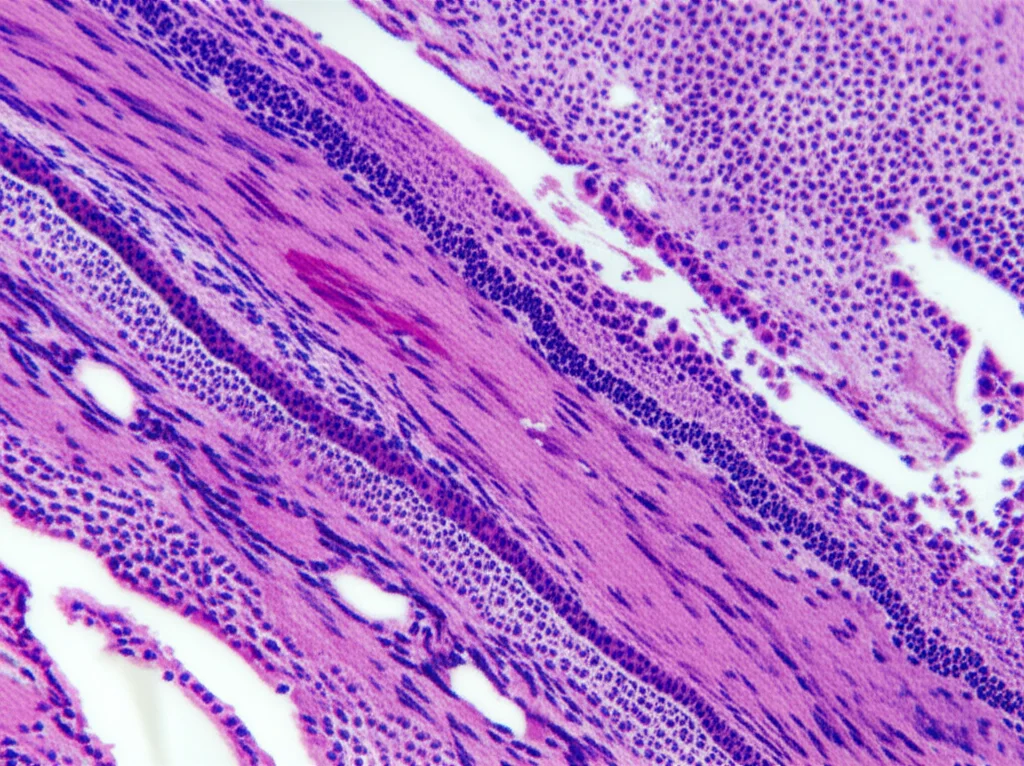

Inizialmente, i medici avevano pensato alla sindrome di Sweet, ma una biopsia cutanea ha tolto ogni dubbio: si trattava proprio di geloni. La cosa ancora più sorprendente è che le lesioni sono scomparse completamente senza alcun trattamento specifico. Tutto risolto? Nemmeno per sogno! Dopo aver ricevuto la seconda dose di vaccino, il 18 dicembre, ecco che le stesse identiche eruzioni cutanee sono ricomparse, nelle stesse zone. Un chiaro segnale che, in questo caso, il vaccino sembrava proprio essere il grilletto.

La risposta immunitaria scatenata dal vaccino a mRNA contro il COVID-19, quindi, potrebbe essere simile a quella che si verifica dopo l’infezione naturale, e in entrambi i casi può portare alla comparsa dei geloni. Studi istopatologici su lesioni da geloni post-vaccino hanno mostrato alti livelli della proteina A di resistenza al mixovirus (MxA) nella pelle. Questa proteina è un marcatore dell’attivazione locale della via dell’interferone di tipo I, proprio come si osserva nei geloni associati all’infezione da COVID-19.